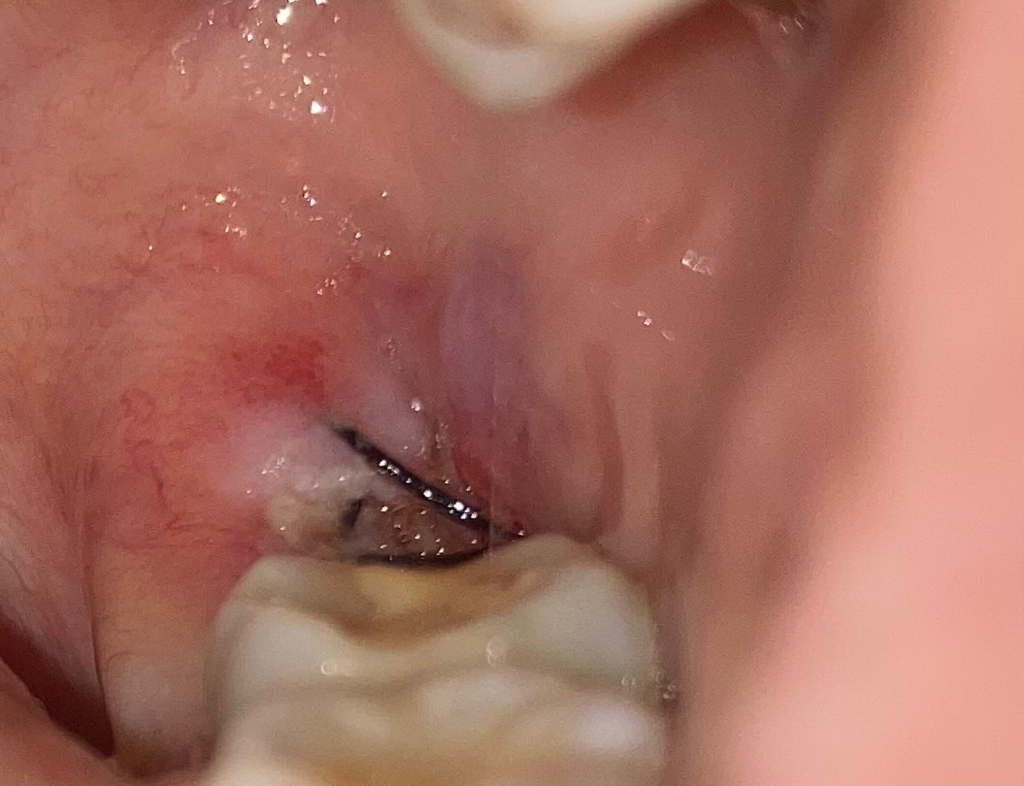

화요일 오전에 사랑니 두 개를 발치 했습니다 한 개는 매복인데 지금 막 입에서 쓴 맛이 나는데 치과에서는 실밥 때문에 그럴 수도 있다 했는데.. 불안해서용 ㅠㅠ 괜찮은건가요?

사진 방금 상태인데 잘 낫고 있나요?

사진 상으로 보아서는 크게 문제점이 보이지 않습니다. 발치 부위가 크다면 1~2주 정도는 통증이 나타날 수 있습니다. 외관상으로 보이는 부분에는 문제가 없을 수 있으나 지속적으로 불편감이 크다면 다시 검사를 해보는 것을 권해드립니다.

사진상으로 보면 크게 문제가 잇어 보이진 않습니다. 잘 낳고 잇어 보이고 실밥때문에 그럴수 잇으니 걱정은 하지 않으셔도 될것같습니다.

사랑니 발치 부위의 삼출액에 의해 쓴맛이 날수 있고 문제가 되지는 않으며.. 잘 치유되고 있는것 같습니다.